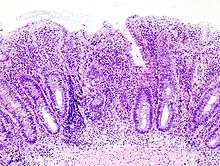

Histologic

Biopsies of the mucosa are taken to definitively diagnose UC and differentiate it from Crohn's disease, which is managed differently clinically. Microbiological samples are typically taken at the time of endoscopy. The pathology in ulcerative colitis typically involves distortion of crypt architecture, inflammation of crypts (cryptitis), frank crypt abscesses, and hemorrhage or inflammatory cells in the lamina propria. In cases where the clinical picture is unclear, the histomorphologic analysis often plays a pivotal role in determining the diagnosis and thus the management. By contrast, a biopsy analysis may be indeterminate, and thus the clinical progression of the disease must inform its treatment.